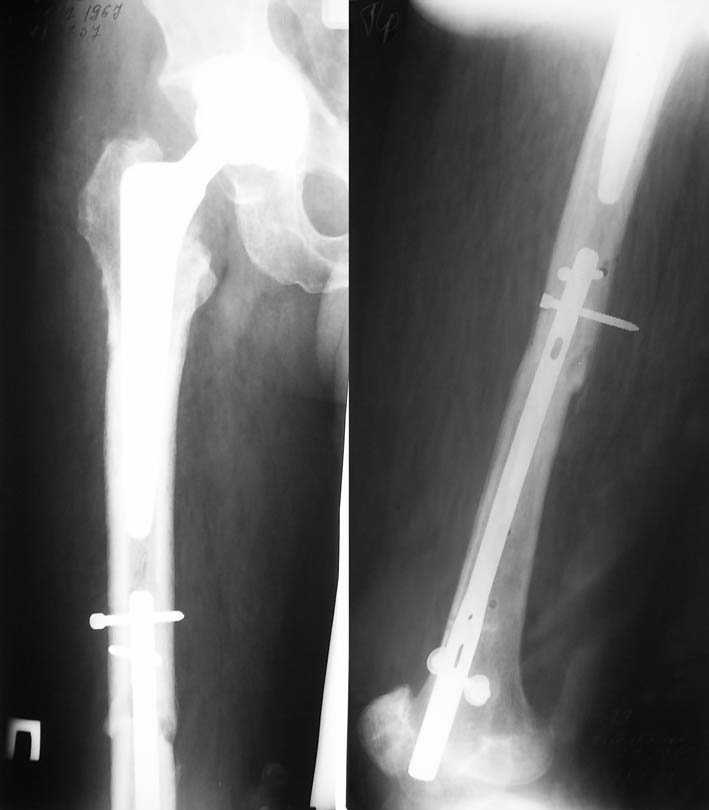

Ошибки случаются, когда игнорируются правила обследования больных с переломом бедра. Часто, когда "экономят" рентген пленки и снимают без надлежащих захватов сустава.

Одним из "золотых" правил при лечении переломов бедра в обязательном порядке до операции необходимо убедиться в отсутствии или наличии перелома шейки.

Отдельный снимок шейки или ЭОП является стандартом обследования. Все сомнительные рентген снимки проверяются тщательно дополнительными срезами КТ.

Из-за опасности вторичного смещения переломов "без смещения" во время интрамедуллярных манипуляций, особенно при ретроградном введении, необходимо каждый случай протоколировать с описанием состояния шейки после операции.

Установленный в бедро штифт, без стимуляции, не гарантирует сращение.

А не опорная болтающаяся конечность с большим рычагом усложнит состояние перелома шейки и поэтому ипсилатеральные переломы, тем более ятрогенные, очень часто осложняются двойными ложными суставами.